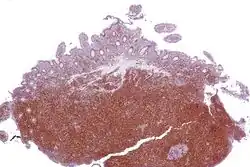

| Micrograph showing mantle cell lymphoma (bottom of image) in a biopsy of the terminal ileum. H&E stain. | |